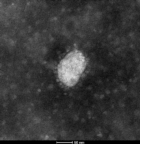

当前,实验室联合广州海关技术中心已完成对该病毒株的全基因组序列测定,并利用间接免疫荧光实验结果显示患者血浆可识别该分离株感染细胞(图1),病毒粒子可在电镜下观察到,具有冠状病毒典型结构(图2)。

图2. 负染电镜结果